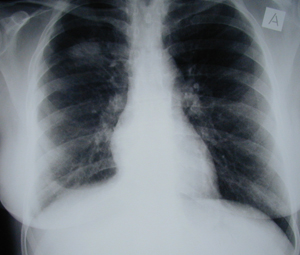

Εικόνα 1

Οπισθιοπροσθία ακτινογραφία του θώρακος. Διακρίνονται δύο μεγάλες κύστες εχινοκόκκου του δεξιού πνεύμονος, μια στον άνω και η άλλη στον κάτω λοβό.